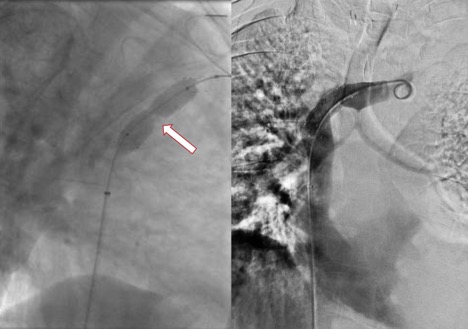

Figure 3. Stent deployment using a 14 x 40 mm self-expanding nitinol stent across the stenotic portion of the peripheral SVC before (left) and after (right) balloon dilation of the stent. Note the robust waist of the angioplasty balloon corresponding to the critical stenosis on preprocedural corss-sectional imaging. The initial pressure gradient across the stenosis was 21 mm Hg. Following stent deployment the pressure gradient was 1 mm Hg.

Subsequently, the decision was made to proceed with a venogram and possible SVC stent placement. If this were unsuccessful, he would undergo thoracoscopic thoracic duct ligation. He was found to have hemodynamically significant stenosis of the superior SVC resulting in a 21 mm Hg pressure gradient between the left innominate vein and central SVC. He underwent successful stent placement with decompression of previously visualized left thoracic venous collaterals (Figure 3). After stent placement the pressure gradient was reduced to 1 mm Hg. The patient subsequently has remained stable, with resolution of his chylothorax without the need for further interventions.